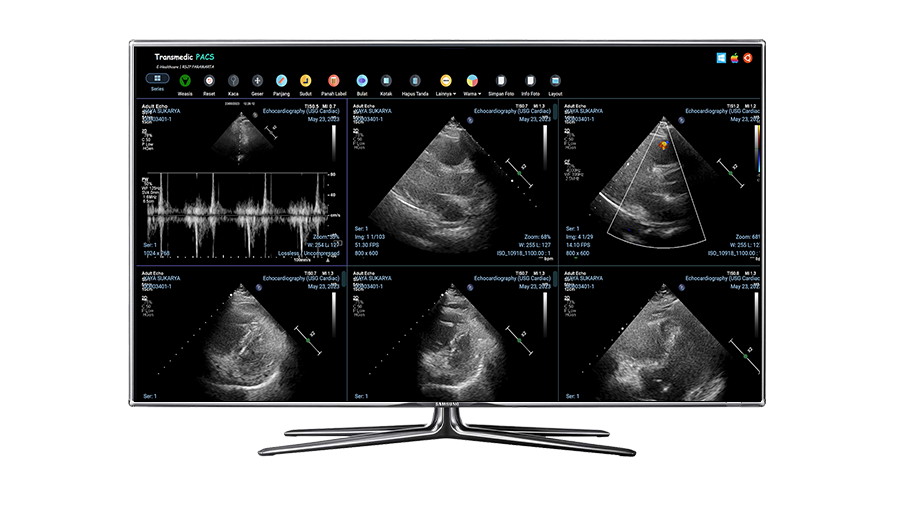

PACS adalah sistem yang berfungsi untuk mengolah, menyimpan, dan mendistribusikan data gambar medis yang diperoleh dari hasil pemeriksaan pasien dengan menggunakan alat pencitraan kesehatan.

Lebih Lanjut